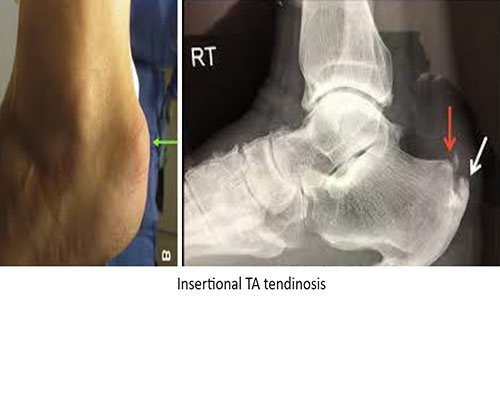

Heel pain is the most common symptom of foot and ankle outpatients. Heel pain usually presents with pain at bottom of heel which is commonly plantar fasciitis or at the back of the heel which is commonly Achilles tendinosis. But all heel pain are not plantar fasciitis or Achilles tendinosis, there are causes other than these two also. Sometimes atrophy of plantar fat pad, traumatic inflammation of fat pad, or lateral plantar nerve compression can also elicit pain at the bottom of foot. Compression of the lateral plantar nerve is the most disabling and difficult differential diagnosis of plantar fasciitis. Achilles tendinosis or more precisely insertional Achilles tendinosis can be associated with few other abnormalities around it like prominence of heel bone; ‘Haglund deformity,’ inflamed bursa around the tendon. A tight gastrocnemius muscle is the common factor for most of these heel pain, which causes restricted ankle dorsiflexion in extended knees and produces overloading. There is common misbelief that bone spur causes pain, but it’s not true. It is the degenerated plantar fascia and Achilles tendon which initiates the pain.